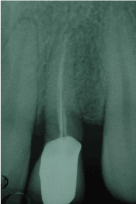

After evaluating different therapeutic options, it was decided to extract the tooth and place an immediately loaded implant. (Figure 2).

Figure 2. After evaluating different therapeutic options, it was decided to extract the tooth and place an immediately loaded implant.